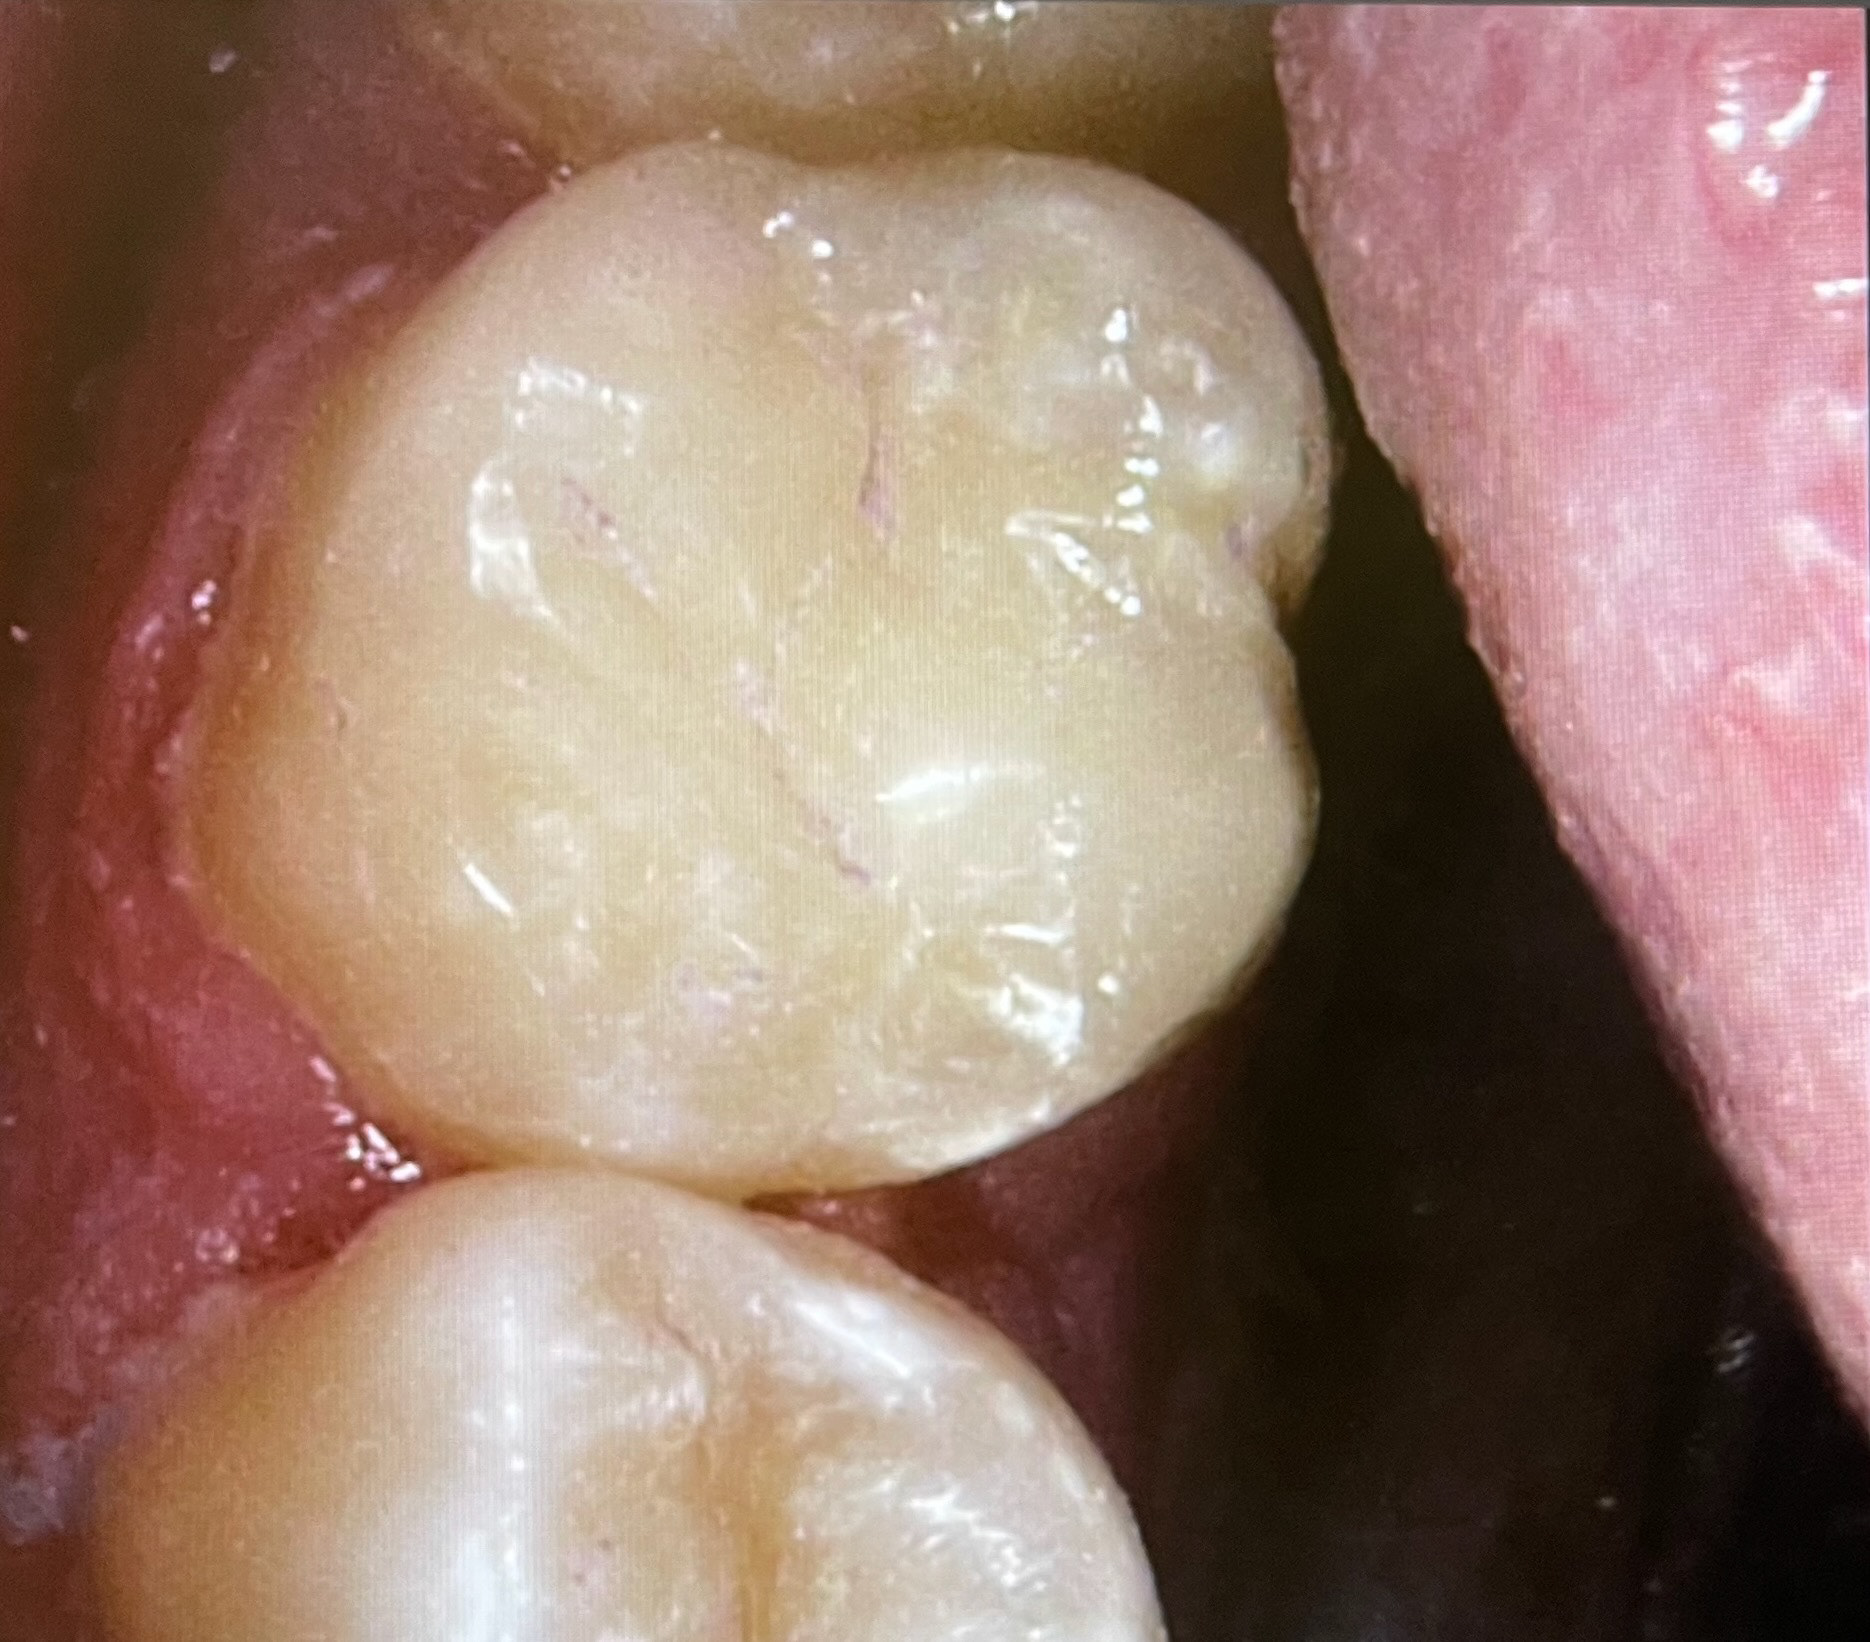

16 Pre-op